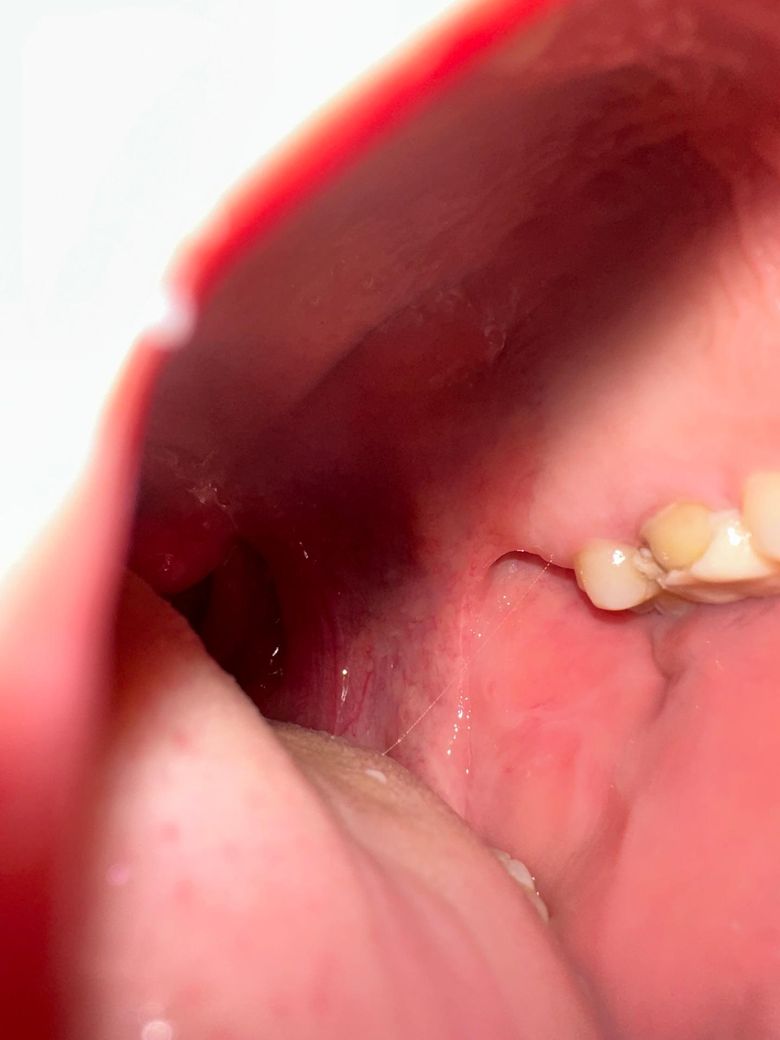

크라운 치료 전 임시치아 깨짐으로 문의드립니다.

오늘 오후 5시 반쯤 저녁 먹는데 임시치아 옆면 일부가 깨졌습니다.

(사진 첨부 했습니다.)

• 1번 째 사진

임시치아가 깨졋다고 해서 치아가 이동하거나 그렇진 않으니 치과에 가셔서 다시 임시치아를 만드시면될것같습니다.

양 옆 치아와의 컨택부위는 임시치아가 남아있으니 괜찮습니다. 신경치료가 안된 치아라면 저 상태에서 좀 시릴 수 있으나 하루뒤에 가니 큰 상관없습니다.